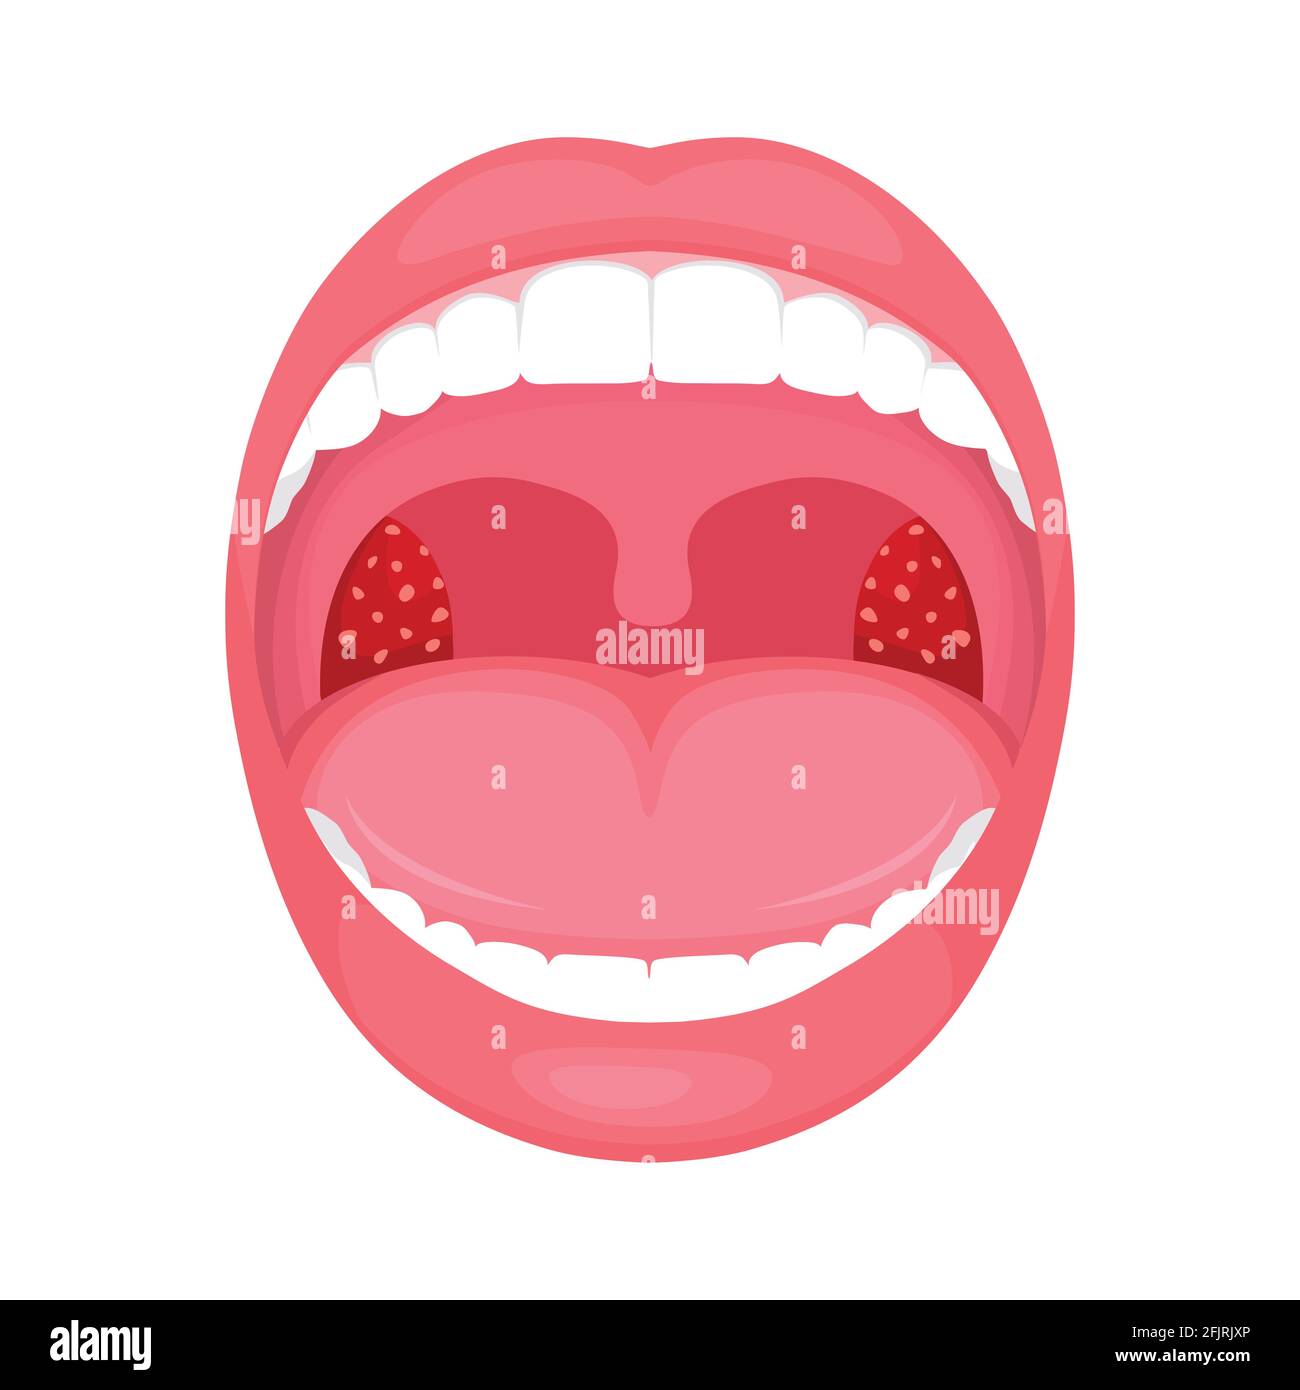

vektor-Illustration einer Kehle bakterielle und virale Infektion, Mandeln Entzündung. Stock Vektorhttps://www.alamy.de/image-license-details/?v=1https://www.alamy.de/vektor-illustration-einer-kehle-bakterielle-und-virale-infektion-mandeln-entzundung-image424632398.htmlRF2FJRJXP–vektor-Illustration einer Kehle bakterielle und virale Infektion, Mandeln Entzündung.

Halsschmerzen im Mund, Nahaufnahme. Erkrankungen des Rachens und der Schleimhaut, Rötung der Kehle und Mandeln, das Phänomen der Stomatitis und Stockfotohttps://www.alamy.de/image-license-details/?v=1https://www.alamy.de/halsschmerzen-im-mund-nahaufnahme-erkrankungen-des-rachens-und-der-schleimhaut-rotung-der-kehle-und-mandeln-das-phanomen-der-stomatitis-und-image397735116.html